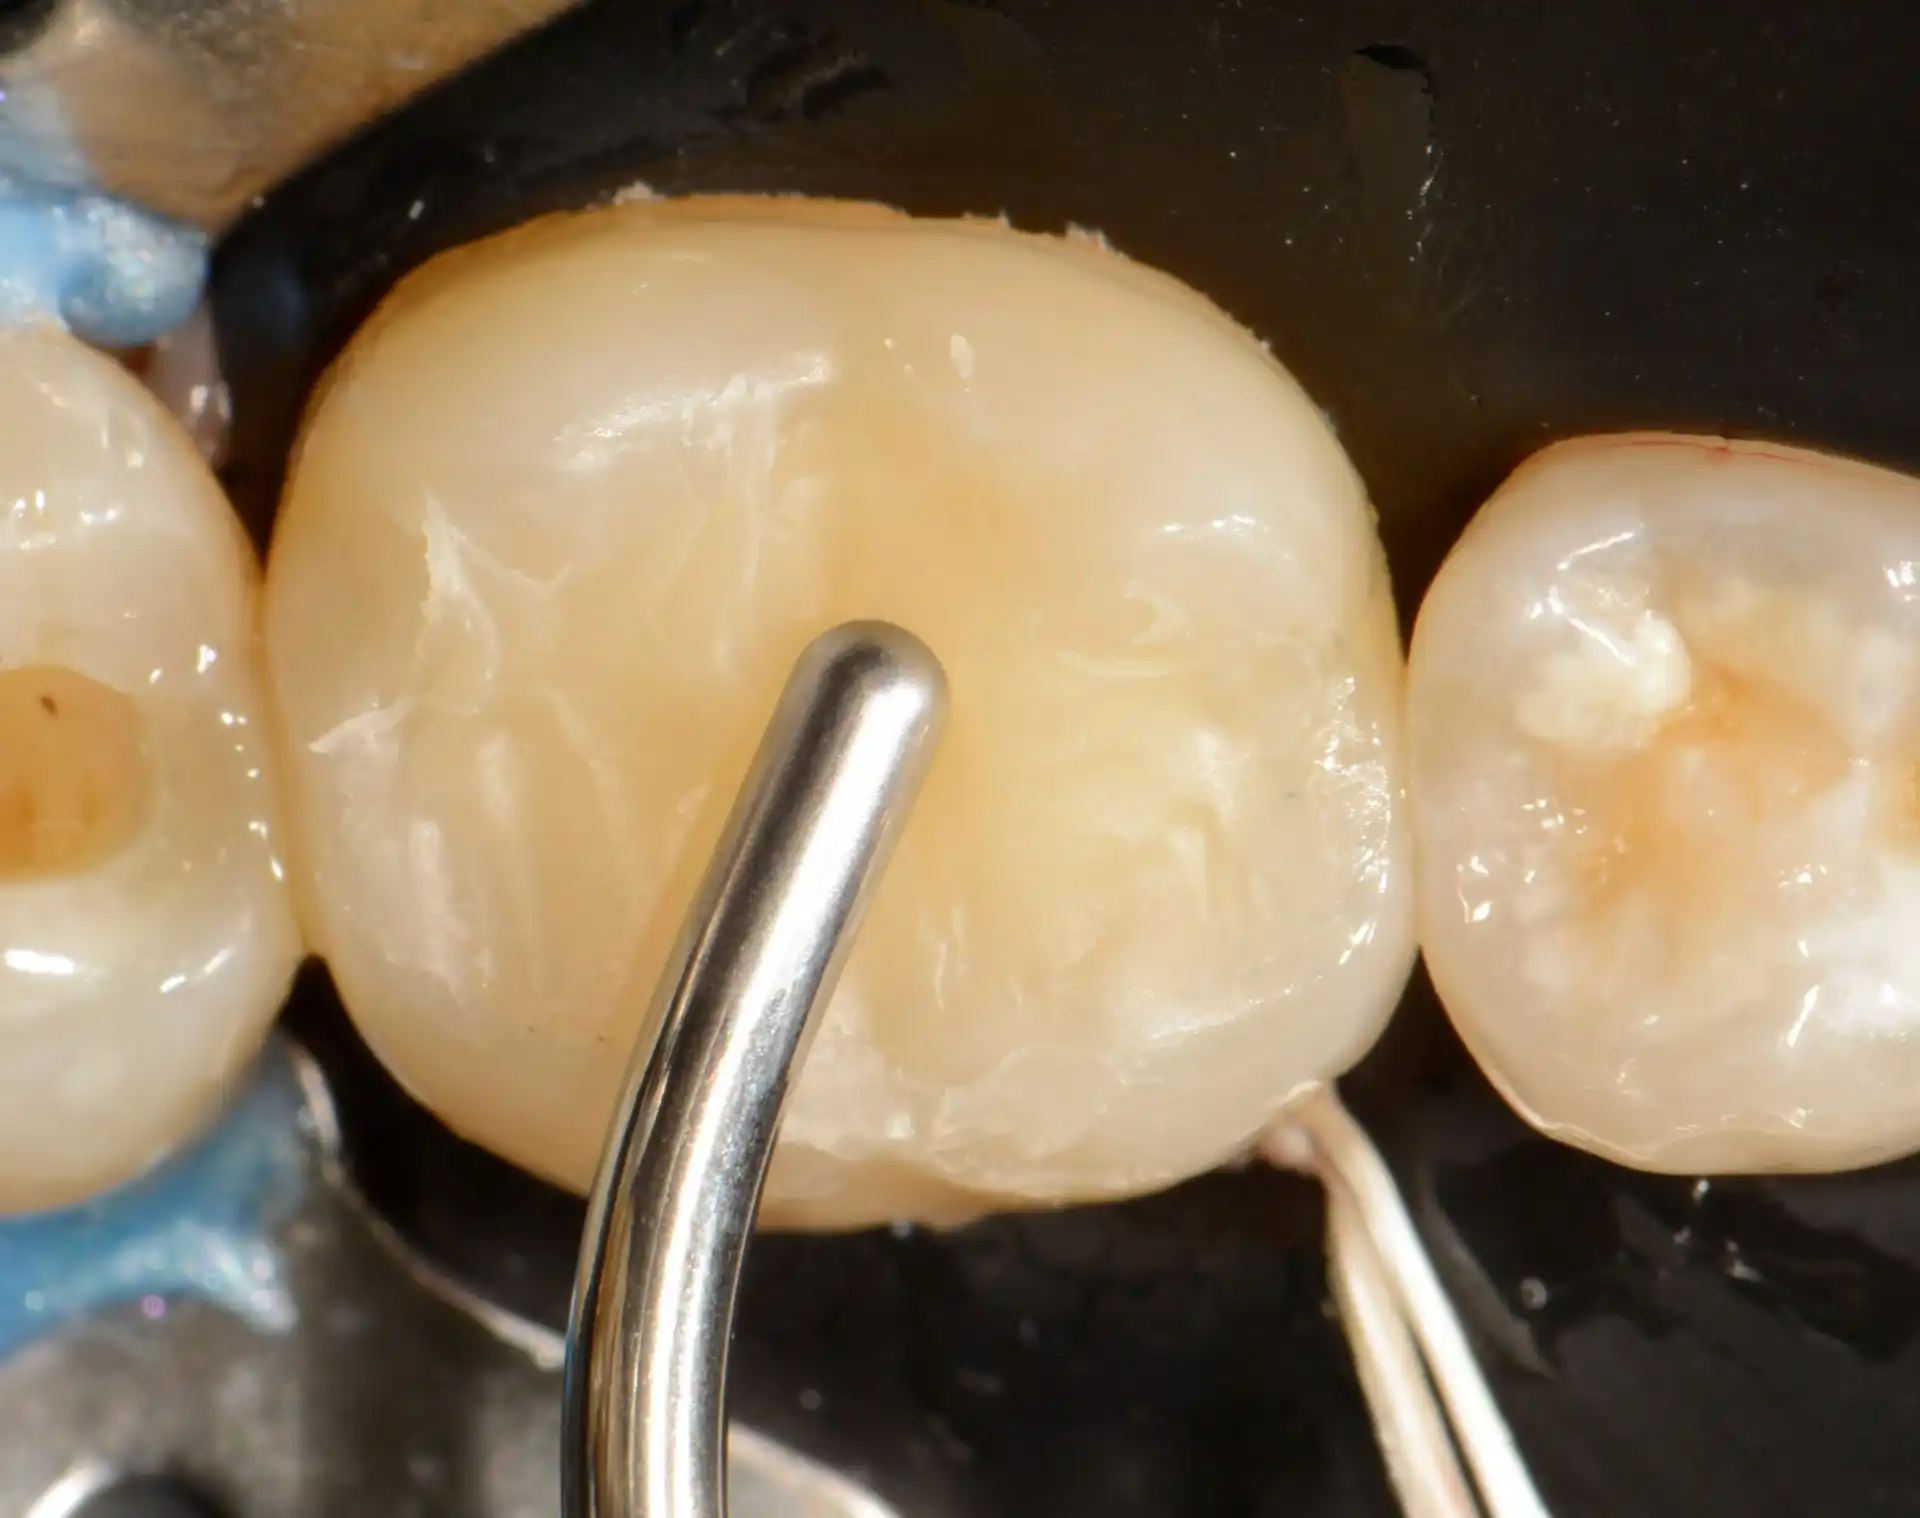

Confira este caso clínico de restauração dentária posterior, terceiro molar, com a resina tipo Bulk da 3M.